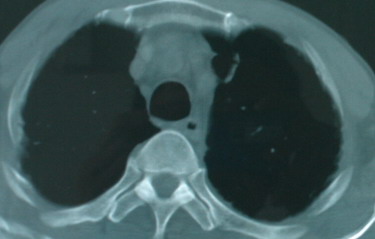

以下是引用卜一在2008-6-3 19:33:00的发言:[br]双肺结节,以双上肺分布为多,期间搀杂片状致密影及索条致密影。考虑:继发性肺结核伴血型播散可能性大。不除外肺泡ca的可能!另:椎体退变!

以下是引用panyishengct在2008-6-3 21:09:00的发言:[br]双上肺弥漫性小结节影,纵隔窗内钙化淋巴结影,考虑矽肺或/和tb可能性较大,不除外肺ca可能。腰椎考虑退变。 [br][br]